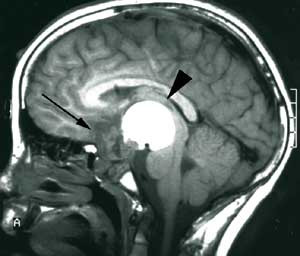

Pasienten ble henvist til Nevrokirurgisk avdeling, Rikshospitalet for vurdering med tanke på ytterligere kirurgi. Det forelå nå imidlertid en betydelig tumordestruksjon og invasjon i clivus av solide tumorkomponenter og ny cyste posterokaudalt mot 3. ventrikkel/hypothalamus og pons (fig 3a). Klinisk var pasienten også i meget rask forverring og hadde preoperativt redusert bevissthet, sløvet tale, ustø gange og urininkontinens.

Pasienten er ved tremånederskontroll betydelig restituert og har kun en mindre ekstremitetsparese. Som før den siste operasjonen er han blind og fullstendig hormonsubstituert. Postoperativ MR-undersøkelse viser ikke tegn til resttumor (fig 3b).